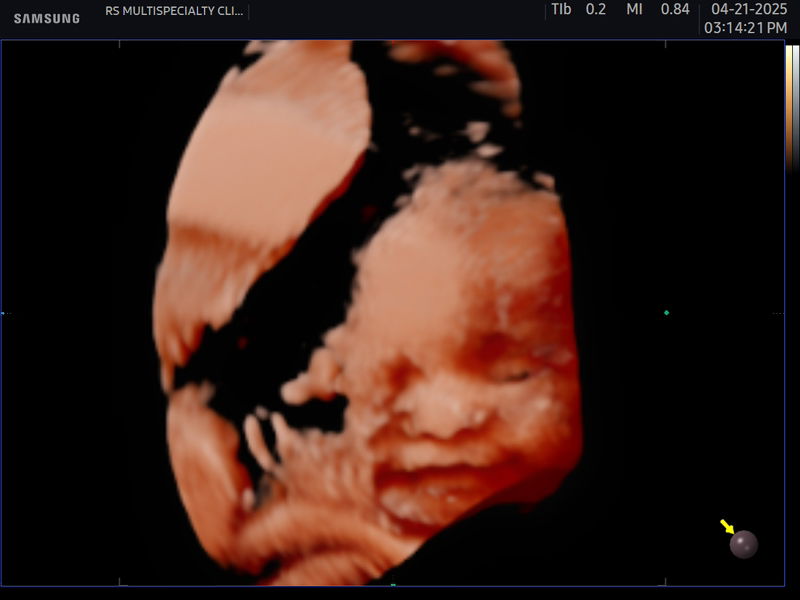

Greatest Blessing My Twins

these are my twins born exactly 38 weeks gestation. 1 month old sila sa pic. congrats mommy!

Momma of Twins